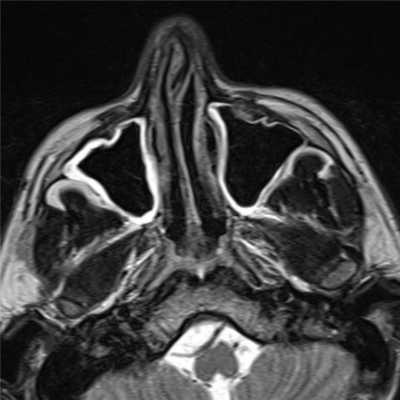

(Слева) При аксиальной МРТ Т1 С+ определяется контрастное усиление в центре большой экстраназальной глиомы, слегка смещенной от средней линии. Накопление контраста в экстраназальной глиоме нетипично.

(Справа) При аксиальной МРТ Т1 С+ визуализируется хорошо отграниченная срединная экстраназальная глиома спинки носа с диффузным контрастным усилением. Настолько выраженное накопление контраста - редкий признак глиомы носа.